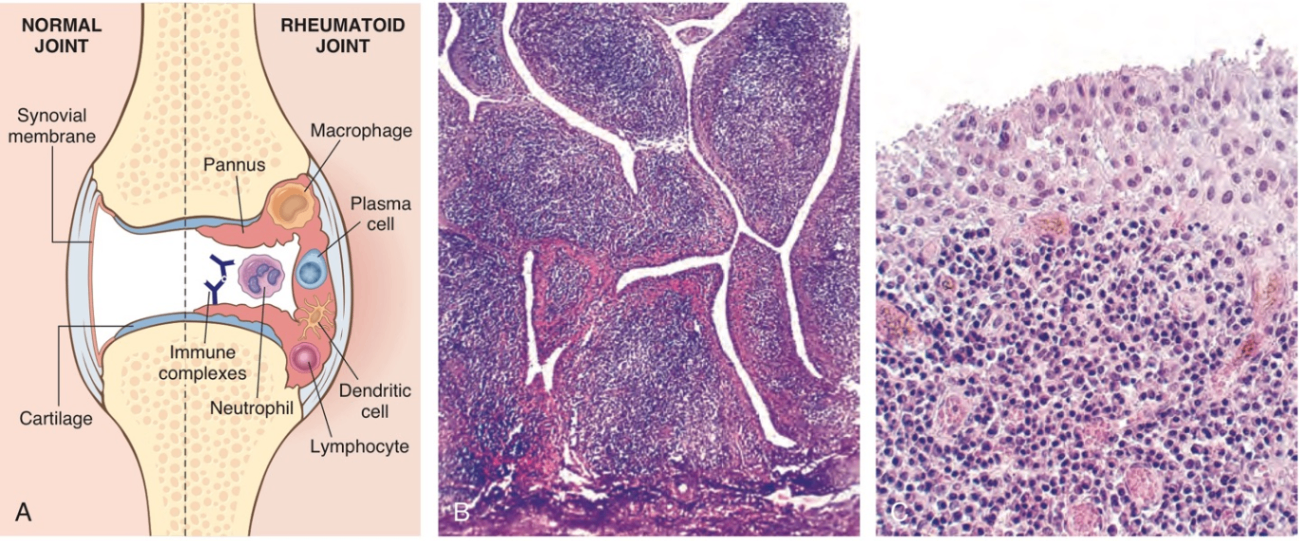

2. 류마티스 관절염 (Rheumatoid Arthritis)

관절을 주로 침범하는 만성 자가면역 질환으로, 화농을 동빈하지 않는 증식성(proliferative) 및 염증성(inflammatory) 활막염

(3) 조직학적 소견

• RA는 특징적으로 다음과 같은 조직학적 소견을 보인다:

활막세포의 과형성(hyperplasia) 및 증식이 나타나며, 진행되면 융모(villi) 구조 형성

활막에 CD4+ T helper cell, B cell, 형질세포, 수지상세포, 대식세포 등이 침윤해 lymphoid follicle 형성

혈관신생(angiogenesis)에 의해 혈관 분포(vascularity) 증가

관절 및 활막 표면에 fibrinopurulent exudate

파골세포(osteoclast)의 활성에 의해 활막이 subchondral bone을 침범해 관절 주위를 침식하고 subchondral cyst 형성

• 이러한 변화들이 함께 작용하여 pannus을 형성함. 이는 edematous synovium, granulation tissue, 그리고 fibroblast로 구성된 조직 덩어리로, 관절 연골을 침범하여 점진적인 연골 침식을 일으킴

• 질병이 진행되며 pannus는 인접한 뼈들을 연결하게 되고 fibrous ankylosis을 형성함. 이는 ossification이 되어 결국 bony ankylosis, 즉 뼈의 유착으로 이어지게 됨

Robbins and Cotran Pathologic Basis of Disease, 10e, pg 1201